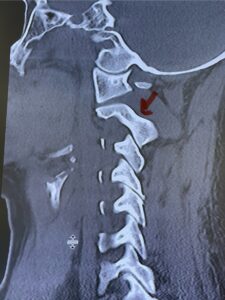

Fig. 6a: Sagittal cervical CT scan demonstrating an abnormally thin right C2 isthmus prohibiting safe placement of screw (red arrow). Notice the vertebral foramen eroding the isthmus bone structure (red dot).